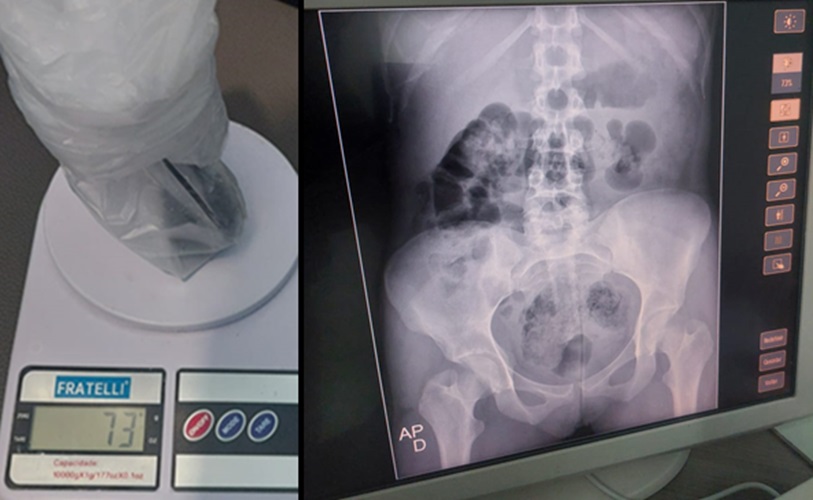

O flagrante ocorreu durante a passagem das jovens pelo aparelho de Raio X da unidade prisional. Uma delas estava portando 73 gramas de maconha no ânus, enquanto a outra carregava dois pacotes no mesmo local, contendo aproximadamente 50 gramas de maconha e um pouco mais de 50 gramas de cocaína.

Após a descoberta, ambas foram encaminhadas ao Hospital Regional de Cajazeiras para a retirada dos entorpecentes. A segunda jovem, que portava os dois pacotes, precisou passar por um procedimento cirúrgico devido ao volume considerável.